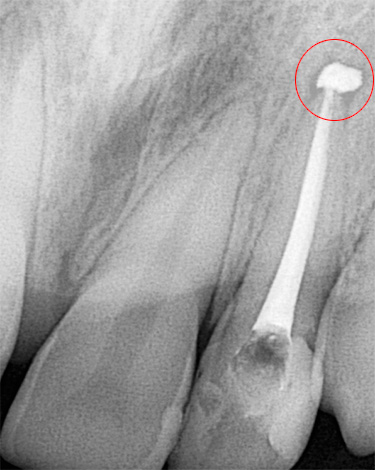

O diagnóstico por raio-X também é importante. Na pulpite fibrosa crônica, uma cavidade profunda de cárie, que quase sempre se comunica com a câmara pulpar, geralmente pode ser observada na radiografia de um dente doente. Às vezes, uma ligeira expansão do espaço periodontal (o espaço entre a raiz e o osso dos alvéolos nos quais está fixado) é fixada.